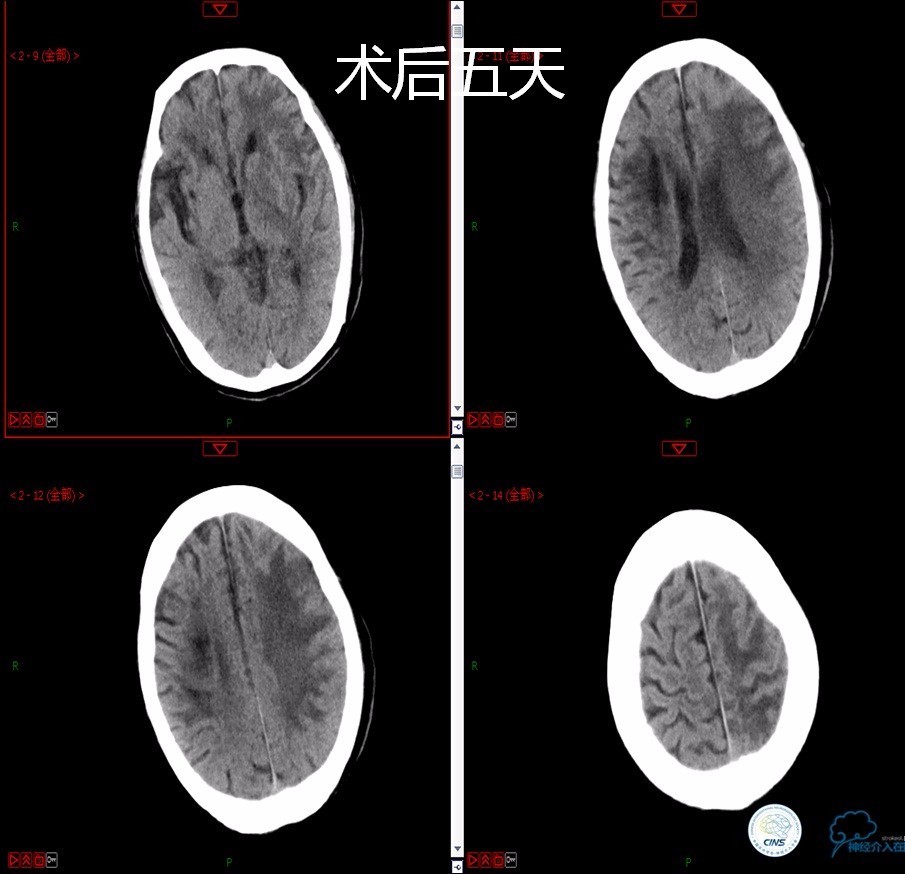

》患者术后4小时出现右侧肢体无力,伴有癫痫样症状。

》考虑小栓子脱落,术中曾有后扩。

》术后严密控制血压,未出现明显血压波动。

》术后三小时,患者出现恶心呕吐,伴有意识丧失。

》出血原因?侧支代偿不佳!